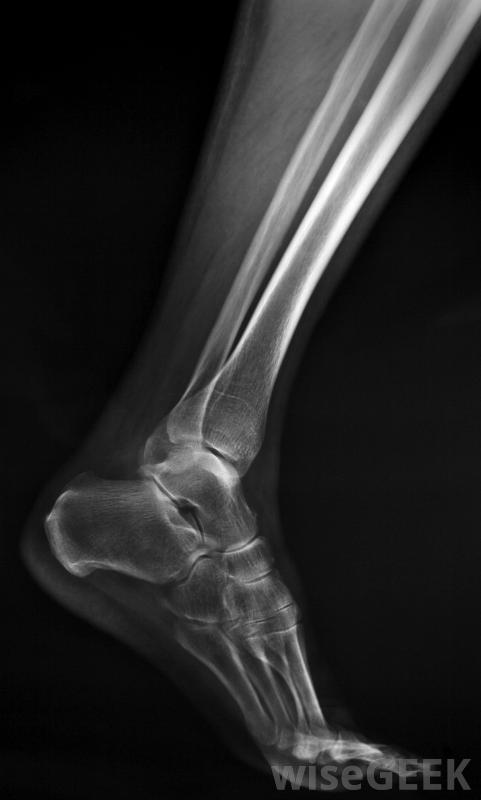

骨囊肿可通过x光等影像学检查发现。5至15岁的儿童最常受到此类囊肿的影响。然而,年龄较大的儿童和成人,也可能被诊断为单纯性骨囊肿。不过,这些人更容易在扁骨(包括骨盆和肋骨)中发生囊肿。在老年人的颌骨或跟骨也有可能形成单纯性骨囊肿单纯性骨囊肿的病因通常不得而知。然而,一些医生却有一些理论。一些医生认为这些囊肿可能是由生长板或血液循环问题引起的。还有一些证据表明,反复的创伤,如大量骨折,也可能使人有患单纯性骨囊肿的风险。通常,单纯的骨囊肿被认为是良性的。这意味着它通常不会影响身体中除了含有它的骨头之外的任何其他部位。然而,在某些情况下,它可能会变大。这可能会导致骨内压力增大并导致骨折,但这种情况并非每一例都会发生轻微的单纯性骨囊肿通常没有症状。但是,如果囊肿开始骨折,患者通常会感到疼痛。该区域也可能出现肿胀简单的骨囊肿除非恶化并引起问题,否则通常不会被发现。这种类型的骨囊肿通常是通过影像学检查,如x光片或计算机地形扫描发现的。类固醇注射有时被用来治疗这种情况,因为它们会导致囊肿消失。其他时候,在骨头上钻一个小孔,然后移除囊肿。在这个过程之后,植入供体骨组织来封闭这个洞。